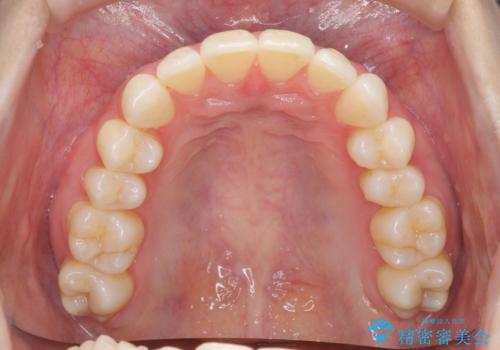

昔ワイヤー矯正をして後戻りした 軽度のがたつき モニター矯正

- 矯正治療後の後戻りを主訴に来院。

特に下の前歯のがたつきを気にされていました。

マウスピース矯正で再矯正を行いました。

再度の後戻りを防ぐため、下顎前歯の裏にはワイヤーを貼る保定を行っています。